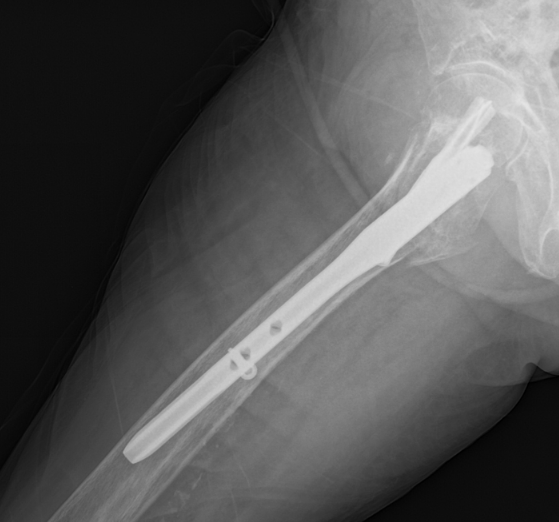

骨科团队迅速评估病情,认为手术治疗是让老人重新站起来的唯一希望,也是降低长期卧床并发症风险的最佳选择。在科主任李忠教授带领下,唐炼副主任医师团队反复研究影像资料,精心设计创伤小、固定可靠的手术方案——微创闭合复位股骨近端防旋髓内钉(PFNA)内固定术。手术仅用时30分钟顺利完成。